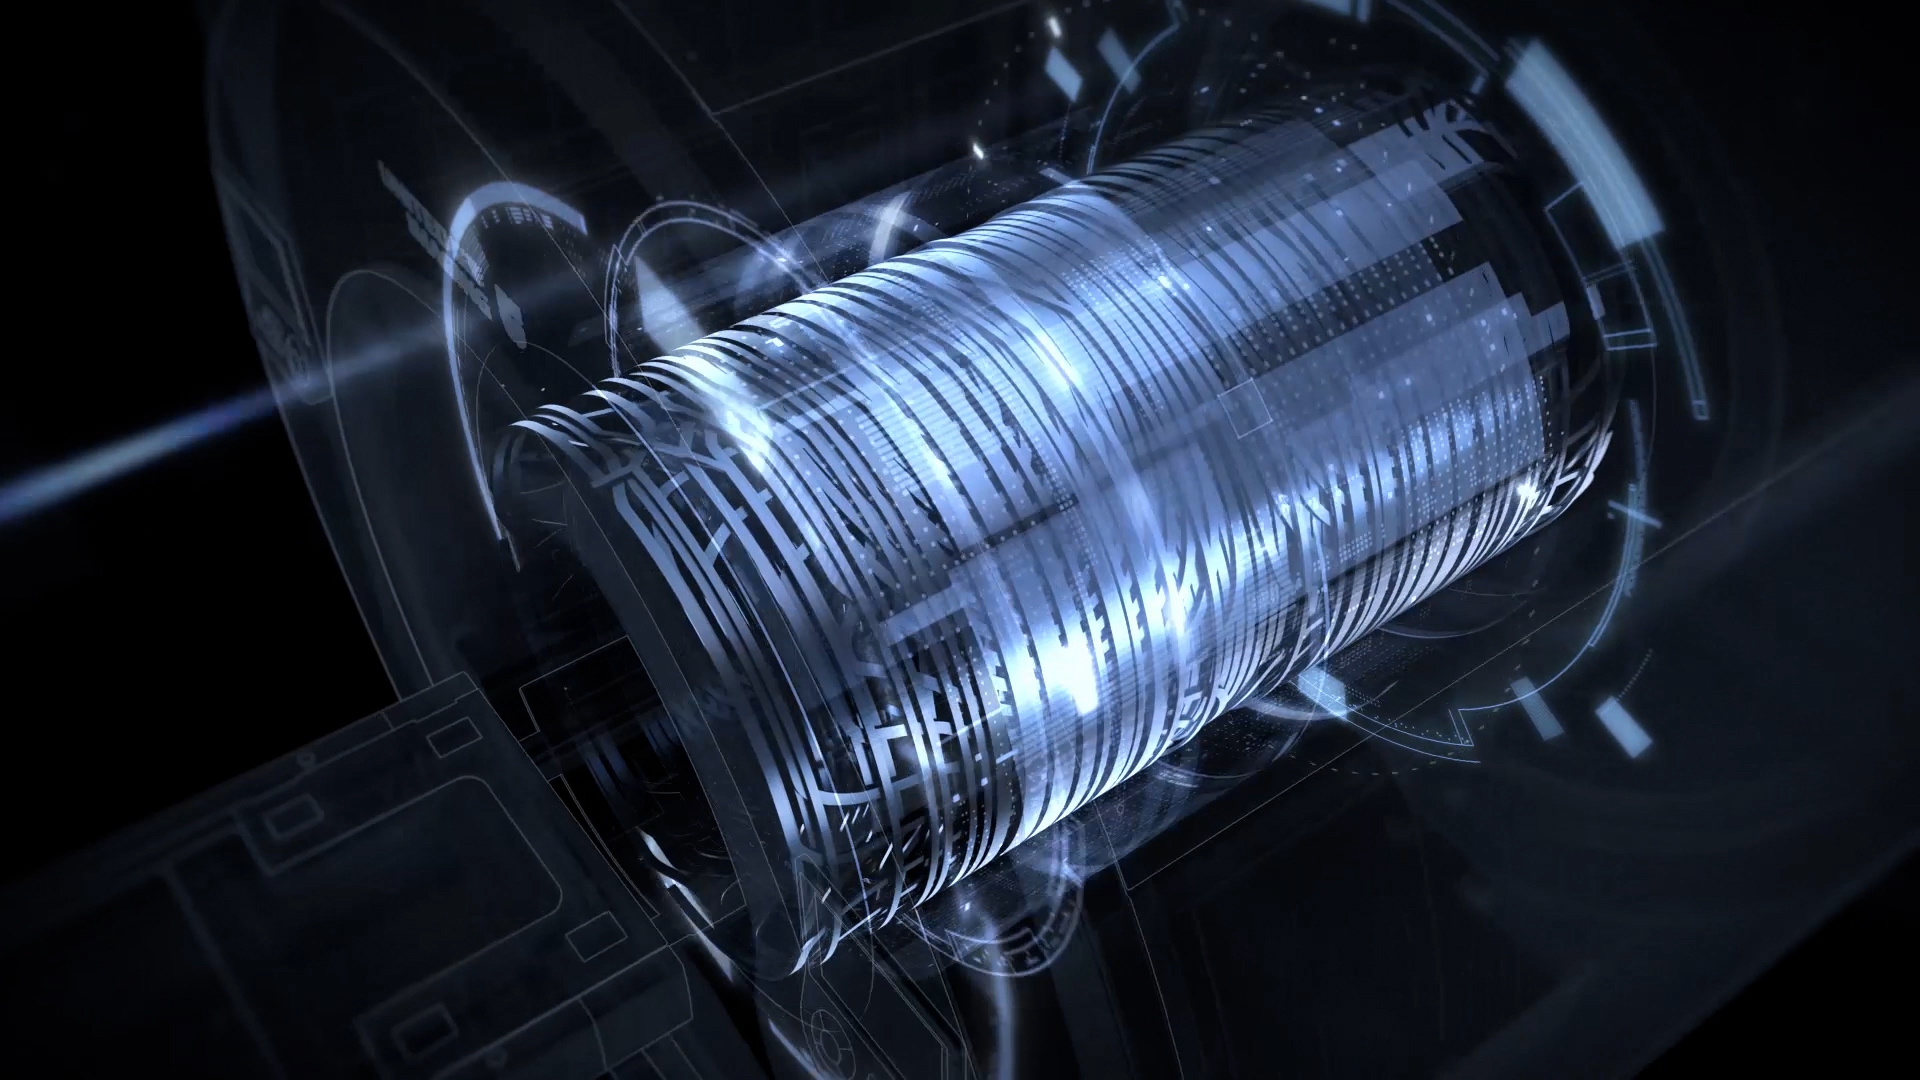

「3.0T级」高性能梯度

uMR 680 磁共振拥有超强劲的梯度「引擎」,搭载了联影自主研发的峰值功率达到2.05 MW的全数字梯度功率放大器,该梯度功率放大器并先后突破了大功率、稳定输出,以及高强度、高线性度、高精度设计及制造等一系列工艺瓶颈,将大孔径1.5T磁共振的梯度性能推向了新的高度。